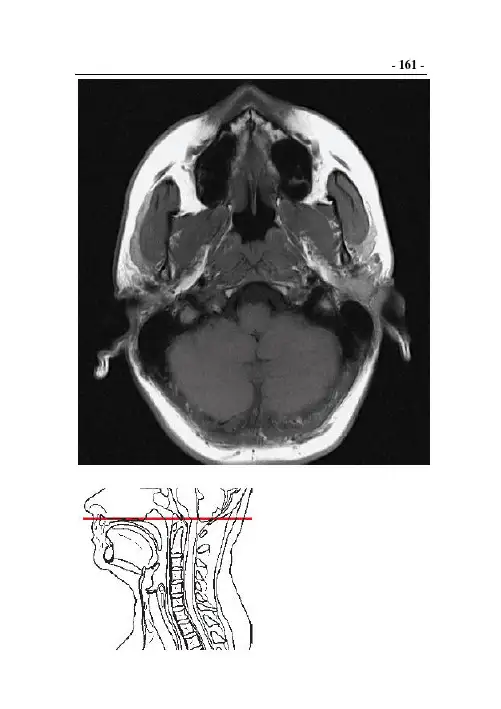

- 161 -- 162 -1. 口轮匝肌2. 提上唇肌3. 上颌骨腭突与切牙管4. 提口角肌5. 上颌窦6. 颧大肌7. 软腭8. 咬肌9. 鼻咽10. 翼内肌11. 颞肌12. 腭帆张肌13. 翼外肌14. 下颌神经15. 咽鼓管16. 上颌动脉17. 头长肌18. 下颌后静脉19. 下颌支20. 岩悬雍垂肌21. 舌咽神经22. 枕骨基底部23. 颈内动脉24. 腮腺25. 迷走神经26. 颈内静脉27. 舌下神经28. 椎动脉29. 脚间池30. 乙状窦31. 乳突小房32. 延髓33. 小脑蚓部34. 小脑扁桃体35. 枕骨36. 小脑半球后叶37. 小脑延髓池38. 头半棘肌- 163 -- 164 -1. 口轮匝肌2. 提口角肌3. 上颌骨腭突4. 硬腭5. 颊肌6. 颧肌7. 软腭8. 面动脉9. 翼外肌10. 咬肌11. 翼内肌12. 颞肌13. 岩悬雍垂肌14. 下颌支15. 头夹肌16. 腭帆张肌17. 头长肌18. 鼻咽19. 寰椎前弓20. 颈内动脉21. 颈内静脉22. 腮腺23. 下颌后静脉24. 迷走神经25. 头外侧直肌26. 舌下神经27. 延髓28. 副神经29. 乳突小房30. 枕骨基底部31. 二腹肌后腹32. 脚间池33. 头夹肌34. 导静脉与髁管35. 小脑扁桃体36. 椎动脉37. 枕骨38. 小脑后叶39. 头半棘肌40. 小脑延髓池- 165 -- 166 -1. 口轮匝肌2. 提口角肌3. 硬腭4. 齿槽突5. 面动脉6. 颊肌7. 软腭8. 咬肌9. 翼外肌10. 下颌支11. 翼内肌12. 腭帆张肌13. 咽上缩肌14. 喉咽15. 头长肌16. 颈内动脉17. 寰椎前弓18. 舌咽神经19. 上颌动静脉20. 迷走神经21. 下颌后静脉22. 舌下神经23. 茎突咽肌24. 副神经25. 腮腺26. 寰椎横突27. 枢椎齿突28. 二腹肌后腹29. 延髓30. 寰椎横韧带31. 椎动脉32. 头外侧直肌33. 寰椎后弓34. 头上斜肌35. 头后小直肌36. 头下斜肌37. 头半棘肌38. 头夹肌- 167 -- 168 -1. 上唇2. 切牙(左1,2)3. 口轮匝肌4. 尖牙(左3)5. 提口角肌6. 前磨牙(左4,5)7. 舌8. 磨牙(6-8)9. 颊肌10. 面动脉11. 悬雍垂12. 咬肌13. 腭帆张肌14. 下颌支15. 咽上缩肌16. 翼内肌17. 头长肌18. 口咽19. 茎突舌肌20. 咽静脉丛21. 茎突咽肌22. 腮腺与下颌后静脉23. 上颌动脉24. 舌咽神经25. 颈内动脉26. 舌下神经27. 寰椎前弓28. 迷走神经29. 横突(孔)30. 副神经31. 二腹肌后腹32. 寰椎侧块33. 胸锁乳突肌34. 枢椎齿突35. 脊髓36. 寰椎横韧带37. 颈深静脉38. 头最长肌39. 斜方肌40. 头下斜肌41. 头半棘肌42. 头夹肌43. 项韧带- 169 -- 170 -1. 口轮匝肌2. 舌(颏舌肌)3. 提口角肌4. 上颚5. 面动脉6. 舌下肌7. 悬雍垂8. 咬肌9. 口咽10. 腭扁桃体11. 翼内肌12. 咽上缩肌13. 腭咽肌14. 颈外动脉15. 头长肌16. 面神经17. 茎突舌骨肌18. 下颌后静脉19. 颈内动脉20. 舌下神经21. 腮腺22. 颈内静脉23. 二腹肌后腹24. 迷走神经25. 颈最长肌26. 副神经27. 肩胛提肌28. 颈长肌29. 胸锁乳突肌30. 椎动脉31. 头最长肌32. 寰椎椎体33. 头夹肌34. 脊髓35. 颈深静脉36. 头下斜肌37. 头半棘肌38. 斜方肌39. 项韧带1. 口轮匝肌2. 降口角肌3. 上颚4. 下颌舌骨肌5. 颏舌肌6. 咬肌7. 舌骨舌肌8. 下颌(下)腺9. 口咽10. 咽上缩肌11. 腭咽肌12. 头长肌13. 咽中缩肌14. 颈外动脉15. 翼内肌16. 腮腺17. 茎突舌肌18. 颈内动脉19. 颈长肌20. 舌下神经21. 寰椎椎体22. 颈内静脉23. 下颌后静脉24. 副神经25. 椎动脉26. 迷走神经27. 胸锁乳突肌28. 颈最长肌29. 头最长肌30. 肩胛提肌31. 脊髓32. 头半棘肌33. 头棘肌与多裂肌34. 颈半棘肌35. 脊椎棘突36. 头夹肌37. 颈深静脉38. 斜方肌39. 项韧带1. 颏肌2. 降口角肌3. 下颚4. 颈阔肌5. 颏舌肌6. 下颌舌骨肌7. 舌骨舌肌8. 会厌9. 舌根10.下颌(下)腺11.茎突舌肌12.口咽13.茎突舌骨肌14.腭咽肌15.二腹肌后腹16.咽中缩肌17.喉咽18.颈外动脉19.头长肌20.喉上神经21.颈长肌22.颈内动脉23.颈外静脉24.颈内静脉25.C3椎体26.副神经27.C4脊神经根28.迷走神经29.脊髓30.胸锁乳突肌31.C3椎板32.椎动脉33.颈深静脉34.肩胛提肌35.棘突36.黄韧带37.头夹肌38.颈棘肌39.项韧带40.头半棘肌41.斜方肌1. 下颌骨2. 降口角肌3. 下颌舌骨肌4. 二腹肌前腹5. 颏舌骨肌6. 舌骨体7. 会厌谷8. 舌骨大角9. 会厌10. 下颌(下)腺11. 喉咽12. 咽下缩肌13. 梨状隐窝14. 颈长肌15. 下颌后静脉16. 甲状腺上动脉17. 颈阔肌18. 头长肌19. 颈总动脉分叉20. 迷走神经21. 颈内静脉22. 脊神经(C3)23. 颈外静脉24. 脊神经(C2)25. 椎动脉26. 胸锁乳突肌27. 脊神经根(C4)28. 椎间盘(C3/4)29. 关节突关节30. 脊髓31. 肩胛提肌32. 黄韧带33. 颈深静脉34. C3后弓35. 头半棘肌36. 颈棘肌37. 斜方肌38. 颈半棘肌39. 头夹肌40. 项韧带1. 甲状舌骨肌2. 胸骨舌骨肌3. 会厌软骨4. 喉前庭5. 喉咽6. 杓状会厌皱襞7. 下颌(下)腺8. 咽下缩肌9. 颈阔肌10.颈总动脉11.C4椎体12.颈长肌13.颈内静脉14.头长肌15.头最长肌16.胸锁乳突肌17.颈外静脉18.脊神经(C4)19.脊髓20.脊神经(C3)21.颈棘肌22.椎动脉23.颈深静脉24.脊神经根(C5)25.颈最长肌26.中斜角肌27.颈半棘肌28.肩胛提肌29.头夹肌30.颈夹肌31.项韧带32.头半棘肌33.斜方肌1. 胸骨舌骨肌2. 甲状舌骨肌3. 甲状软骨4. 颈阔肌5. 喉前庭6. 杓状会厌皱襞7. 喉咽8. 颈前静脉9. 咽下缩肌10.胸锁乳突肌11.颈总动脉12.迷走神经13.颈长肌14.头长肌15.颈内静脉16.脊神经(C4)17.C5横突18.脊神经(C5)19.颈外静脉20.中斜角肌21.C5椎体22.椎动脉23.脊髓24.后斜角肌25.C6后弓26.脊神经根C627.黄韧带28.下关节突29.颈棘肌与多裂肌30.肩胛提肌31.颈半棘肌32.颈最长肌33.头半棘肌34.颈夹肌35.斜方肌36.头夹肌- 181 -- 182 -1. 胸骨舌骨肌2. 甲状舌骨肌3. 肩胛舌骨肌4. 喉5. 甲状软骨6. 颈前静脉7. 颈阔肌8. 梨状隐窝9. 杓状软骨10.甲状腺11.环状软骨12.喉咽13.颈总动脉14.咽下缩肌15.颈内静脉16.迷走神经17.颈长肌18.膈神经19.颈外静脉20.头长肌21.C5椎体22.前斜角肌23.胸锁乳突肌24.后斜角肌25.颈最长肌26.脊神经(C4)27.前后神经根28.中斜角肌29.脊髓30.椎动脉31.颈棘肌与多裂肌32.脊神经(C5)33.颈夹肌34.肩胛提肌35.头半棘肌36.脊椎下关节突37.头夹肌38.脊神经根(C6)39.斜方肌40.C6椎体后弓41.颈半棘肌42.C6棘突- 183 -- 184 -1. 声门2. 环状软骨3. 胸骨舌骨肌4. 杓状软骨5. 声带肌6. 颈前静脉7. 肩胛舌骨肌8. 颈长肌9. 甲状软骨10.头长肌11.甲状舌骨肌12.颈阔肌13.甲状腺14.胸锁乳突肌15.颈总动脉16.脊神经(C4,C5)17.颈内静脉18.椎动脉19.颈外静脉20.脊神经(C6)21.膈神经22.头最长肌23.迷走神经24.关节突关节25.中斜角肌26.颈最长肌27.前斜角肌28.头半棘肌29.后斜角肌30.颈夹肌与头夹肌31.肩胛提肌32.颈棘肌与多裂肌33.后环勺肌34.颈半棘肌35.喉咽36.脊髓37.斜方肌38.C5椎体39.咽下缩肌40.神经根(C7)- 185 -- 186 -1. 喉2. 胸骨舌骨肌3. 声带4. 甲状软骨5. 甲状舌骨肌6. 甲状腺7. 杓状软骨8. 颈前静脉9. 杓横肌10. 颈阔肌11. 颈总动脉12. 胸锁乳突肌13. 颈内静脉14. 膈神经15. 迷走神经16. 头长肌17. 颈外静脉18. 前斜角肌19. 喉咽20. 中斜角肌21. 脊神经(C4,C5)22. 后斜角肌23. 颈长肌24. 脊神经根C625. 头最长肌26. 颈最长肌27. 椎动脉28. 颈夹肌29. 肩胛提肌30. 头半棘肌31. 咽下缩肌32. C5/6椎间隙33. 脊髓34. 颈棘肌与多裂肌35. 黄韧带36. 后椎弓37. 头夹肌38. 斜方肌39. 颈半棘肌- 187 -- 188 -1. 喉2. 甲状软骨3. 甲状杓状肌4. 颈前静脉5. 胸骨舌骨肌6. 杓横肌7. 甲状舌骨肌8. 迷走神经9. 胸骨甲状肌10. 颈阔肌11. 环状软骨12. 咽下缩肌13. 甲状腺14. 颈长肌15. 甲状软骨下角16. 头长肌17. 颈总动脉18. 前斜角肌19. 颈内静脉20. 胸锁乳突肌21. 颈外静脉22. C6椎体23. 膈神经24. C4-6脊神经25. 食管26. 椎动脉27. 中斜角肌28. 头最长肌29. 后斜角肌30. 颈最长肌31. 肩胛提肌32. C7脊神经根33. C7横突与后弓34. 头半棘肌35. 脊髓36. 颈夹肌37. 颈棘肌与多裂肌38. C8前后神经根39. 颈半棘肌40. 斜方肌41. 头夹肌42. 脊椎棘突- 189 -- 190 -1. 胸骨舌骨肌2. 环状软骨3. 气管4. 环甲肌5. 胸骨甲状肌6. 颈阔肌7. 甲状腺8. 颈前静脉9. 肩胛舌骨肌10.迷走神经11.食管12.颈总动脉13.胸锁乳突肌14.颈内静脉15.颈长肌16.膈神经17.颈外静脉18.椎动脉19.前斜角肌20.C4-6脊神经21.C6/7椎间隙22.C7神经根23.中斜角肌24.C6/7关节突关节25.后斜角肌26.头最长肌27.脊髓28.颈最长肌29.头半棘肌30.颈夹肌31.颈棘肌与多裂肌32.肩胛提肌33.斜方肌34.颈半棘肌35.脊椎棘突36.上后锯肌37.菱形小肌38.头夹肌39.项韧带- 191 -- 192 -1. 颈前静脉2. 胸骨舌骨肌3. 胸骨甲状肌4. 颈阔肌5. 甲状腺6. 胸锁乳突肌7. 食管8. 气管9. 颈总动脉10. 迷走神经11. 颈内静脉12. 甲状腺下动脉13. 颈长肌14. 膈神经15. 颈外静脉16. 前斜角肌17. C5-7脊神经18. 椎动脉19. C7椎体20. 脊髓21. 中斜角肌22. 第一肋骨23. 后斜角肌24. 颈椎横突25. C8神经根26. 上后锯肌27. 肩胛提肌28. 颈棘肌与多裂肌29. 颈髂肋肌30. 颈半棘肌31. 颈最长肌32. 棘突间韧带33. 颈夹肌34. 斜方肌35. 头半棘肌36. 菱形小肌37. 头夹肌- 193 -- 194 -1. 甲状腺2. 食管3. 颈前静脉4. 甲状腺下静脉5. 气管6. 颈阔肌7. 胸锁乳突肌8. 颈内静脉9. 迷走神经10. 膈神经11. 颈总动脉12. 前斜角肌13. 椎动脉14. C5-7脊神经15. 颈外静脉16. C8神经根17. 颈长肌18. T1横突19. 中斜角肌20. 肋间肌21. T1椎体商后缘22. 脊髓23. 后斜角肌24. 颈髂肋肌25. 第一肋骨26. 肩胛提肌27. C7/T1椎间隙28. 上后锯肌29. 头半棘肌30. 颈夹肌31. 颈棘肌与多裂肌32. 头夹肌33. 颈半棘肌34. 斜方肌35. 菱形小肌36. 棘突间韧带- 195 -- 196 -1. 颈前静脉2. 气管3. 胸锁乳突肌4. 甲状腺5. 颈总动脉6. 胸骨舌骨肌7. 颈阔肌8. 食管9. 颈内静脉10. 颈长肌11. 迷走神经12. 椎动脉13. 膈神经14. T1椎体15. 颈外静脉16. C5-8颈丛17. 前斜角肌18. 中斜角肌19. T1神经根20. 后斜角肌21. 肋间肌22. 第一肋骨23. T1横突24. 肋椎关节25. 黄韧带26. 脊髓27. 肩胛提肌28. 头半棘肌29. 上后锯肌30. 颈髂肋肌31. 颈半棘肌32. 颈棘肌与多裂肌33. 斜方肌34. 颈夹肌35. 脊椎棘突36. 头夹肌(37. 棘突间韧带38. 菱形小肌- 197 -颈部淋巴结1. 颏下淋巴结2. 颌下淋巴结3. 咽后淋巴结4. 耳前淋巴结5. 颈静脉上组淋巴结6. 颈深淋巴结7. 颈背淋巴结8. 颈前静脉淋巴结9. 颈部表浅淋巴结颈部淋巴结(水平分类)Level1a二腹肌间颏下淋巴结Level1b颌下淋巴结Level2a颈内静脉前、中、后淋巴结Level2b颈内静脉背侧淋巴结Level3沿颈静脉的淋巴结Level5a颈后三角淋巴结,上及环状软骨Level6颈动脉腹侧淋巴结- 198 -颈部淋巴结3.咽后淋巴结6.颈深淋巴结7.颈背淋巴结8.颈前静脉淋巴结 10.喉前淋巴结 11.颈静脉下组淋巴结12.颈前淋巴结 13.气管前淋巴结 14.甲状腺淋巴结 15.气管旁淋巴结 16.锁骨上淋巴结17.颈部表浅淋巴结颈部淋巴结(水平分类)Level3沿颈静脉的淋巴结Level4颈静脉下淋巴结Level5a颈后三角淋巴结,上及环状软骨上缘Level5b颈后三角淋巴结,界至及环状软骨下缘Level6颈动脉腹侧淋巴结- 199 -- 200 -颈部间隙1. 咀嚼间隙(咀嚼肌,下颌体与下颌支,下齿槽神经,上颌动脉,翼丛,舌神经)2. 咽旁间隙(三叉神经,咽动脉)3. 表浅粘膜间隙(粘膜下唾液腺,淋巴组织)4. 咽后间隙5. 腮腺间隙(腮腺,面神经,颈外动脉,下颌后静脉)6. 动脉间隙(颈动脉,颈静脉,颅神经Ⅸ-Ⅻ)7. 椎前间隙(椎前与椎旁肌肉,膈神经)8. 内侧间隙(甲状腺,气管旁间隙)9. 椎周间隙(椎前部)10. 椎周间隙(椎旁部)颈部筋膜A颈筋膜浅层B咽颅底筋膜C颈深筋膜中层D颈动脉间筋膜E颈动脉鞘F颈深筋膜深层1. 舌骨上肌群2. 舌骨体3. 会厌前间隙4. 下颌下腺5. 舌会厌襞6. 会厌谷7. 舌骨大角8. 会厌9. 颈前静脉10. 腮腺11. 喉咽12. 颈外动脉13. 颈内动脉14. C3椎体15. 颈内静脉16. 舌骨下肌群(胸骨舌骨肌与胸骨甲状肌)17. 咽会厌襞18. 咽下缩肌19. 颈动脉叉20. 颈长肌21. 椎动脉1. 甲状舌骨膜2. 舌骨下肌群(胸骨甲状肌,肩胛舌骨肌,甲状舌骨肌)3. 会厌前间隙4. 颈阔肌5. 会厌6. 喉7. 梨状隐窝8. 杓状会厌皱襞9. 颈前静脉10.咽下缩肌11.颈总动脉12.颈长肌13.颈内静脉14.椎动脉15.甲状腺上切迹16.会厌软骨茎17.假声带18.甲状软骨薄板19.甲状软骨上角20.C4椎体1. 舌骨下肌群(胸骨甲状肌,肩胛舌骨肌,甲状舌骨肌)2. 甲状软骨3. 甲状杓状肌4. 喉前庭5. 咽喉周围间隙6. 梨状隐窝7. 杓状软骨结节8. 杓状软骨体9. 甲状软骨上角10.杓横肌11.环状软骨12.颈总动脉13.颈内静脉14.颈长肌15.C4椎体16.椎动脉17.喉结18.声门裂19.声带肌20.真声带21.颈前静脉22.甲状腺23.杓斜肌24.食管25.C5椎体1. 舌骨下肌群(胸骨甲状肌,肩胛舌骨肌,甲状舌骨肌)2. 喉前连合3. 声带肌4. 甲状软骨5. 颈前静脉6. 声门下腔7. 环甲关节8. 环状软骨薄板9. 甲状腺10.咽下缩肌11.颈长肌12.C6椎体13.环甲膜14.咽喉周围间隙15.胸锁乳突肌16.甲状软骨下角17.颈内静脉18.颈总动脉19.食管20.椎动脉1. 腭扁桃体2. 枕骨大孔3. 犁骨4. 前纵韧带5. 鼻咽与颈长肌6. 枢椎齿尖韧带7. 硬腭8. 覆膜9. 切牙管10.后寰枕膜11.口轮匝肌12.寰椎前弓13.软腭14.枕骨下脂肪15.舌与口腔上纵肌16.寰椎横韧带17.舌横肌18.寰椎齿突19.颏舌肌与舌中隔20.项韧带21.下颌骨22.黄韧带23.口咽24.棘间肌25.颏舌骨肌26.杓状横肌与斜肌27.下颌舌骨肌28.C6椎体与椎间盘29.舌骨30.喉31.会厌32.C7棘突33.会厌谷34.咽下缩肌35.甲状软骨36.脊髓37.前庭韧带与喉前庭38.棘突39.声韧带(假声带)40.后纵韧带41.胸骨甲状肌42.前纵韧带43.甲状腺44.食管45.气管46.头臂干。

图4-2-1 颈部正位二、侧位颈椎前方长条形透亮影为咽腔,上达颅底,下续食管,前面与鼻腔、口腔、喉腔相通。

以软腭和会厌上端为界,软腭以上的咽腔为鼻咽,会厌上端以下的咽腔为喉腔,两者之间为口咽。

咽后壁与颈椎椎体前缘之间为咽后间隙。

在舌根下方可见舌骨影。

喉上部有会厌软骨,呈叶片状伸向后上方,远端游离。

在会厌软骨下端的前下方有时可见甲状软骨前缘的阴影。

在甲状软骨阴影内可见一横置的双凸透镜样的透明裂隙为喉室,其上缘为室带(即假声带),室带上方是喉前庭。

在喉前庭阴影内可见自后下向前上走行连接杓状软骨和会厌软骨的杓会厌皱襞。

喉下腔为声带以下到环状软骨下缘的部分,在颈6椎体下缘水平与气管连接(图4-2-2)。

图4-2-2 颈部侧位第三节颈部断面影像解剖颈部CT多为横断面图像,骨结构呈高密度致密影,软组织密度次之,气体密度最低。